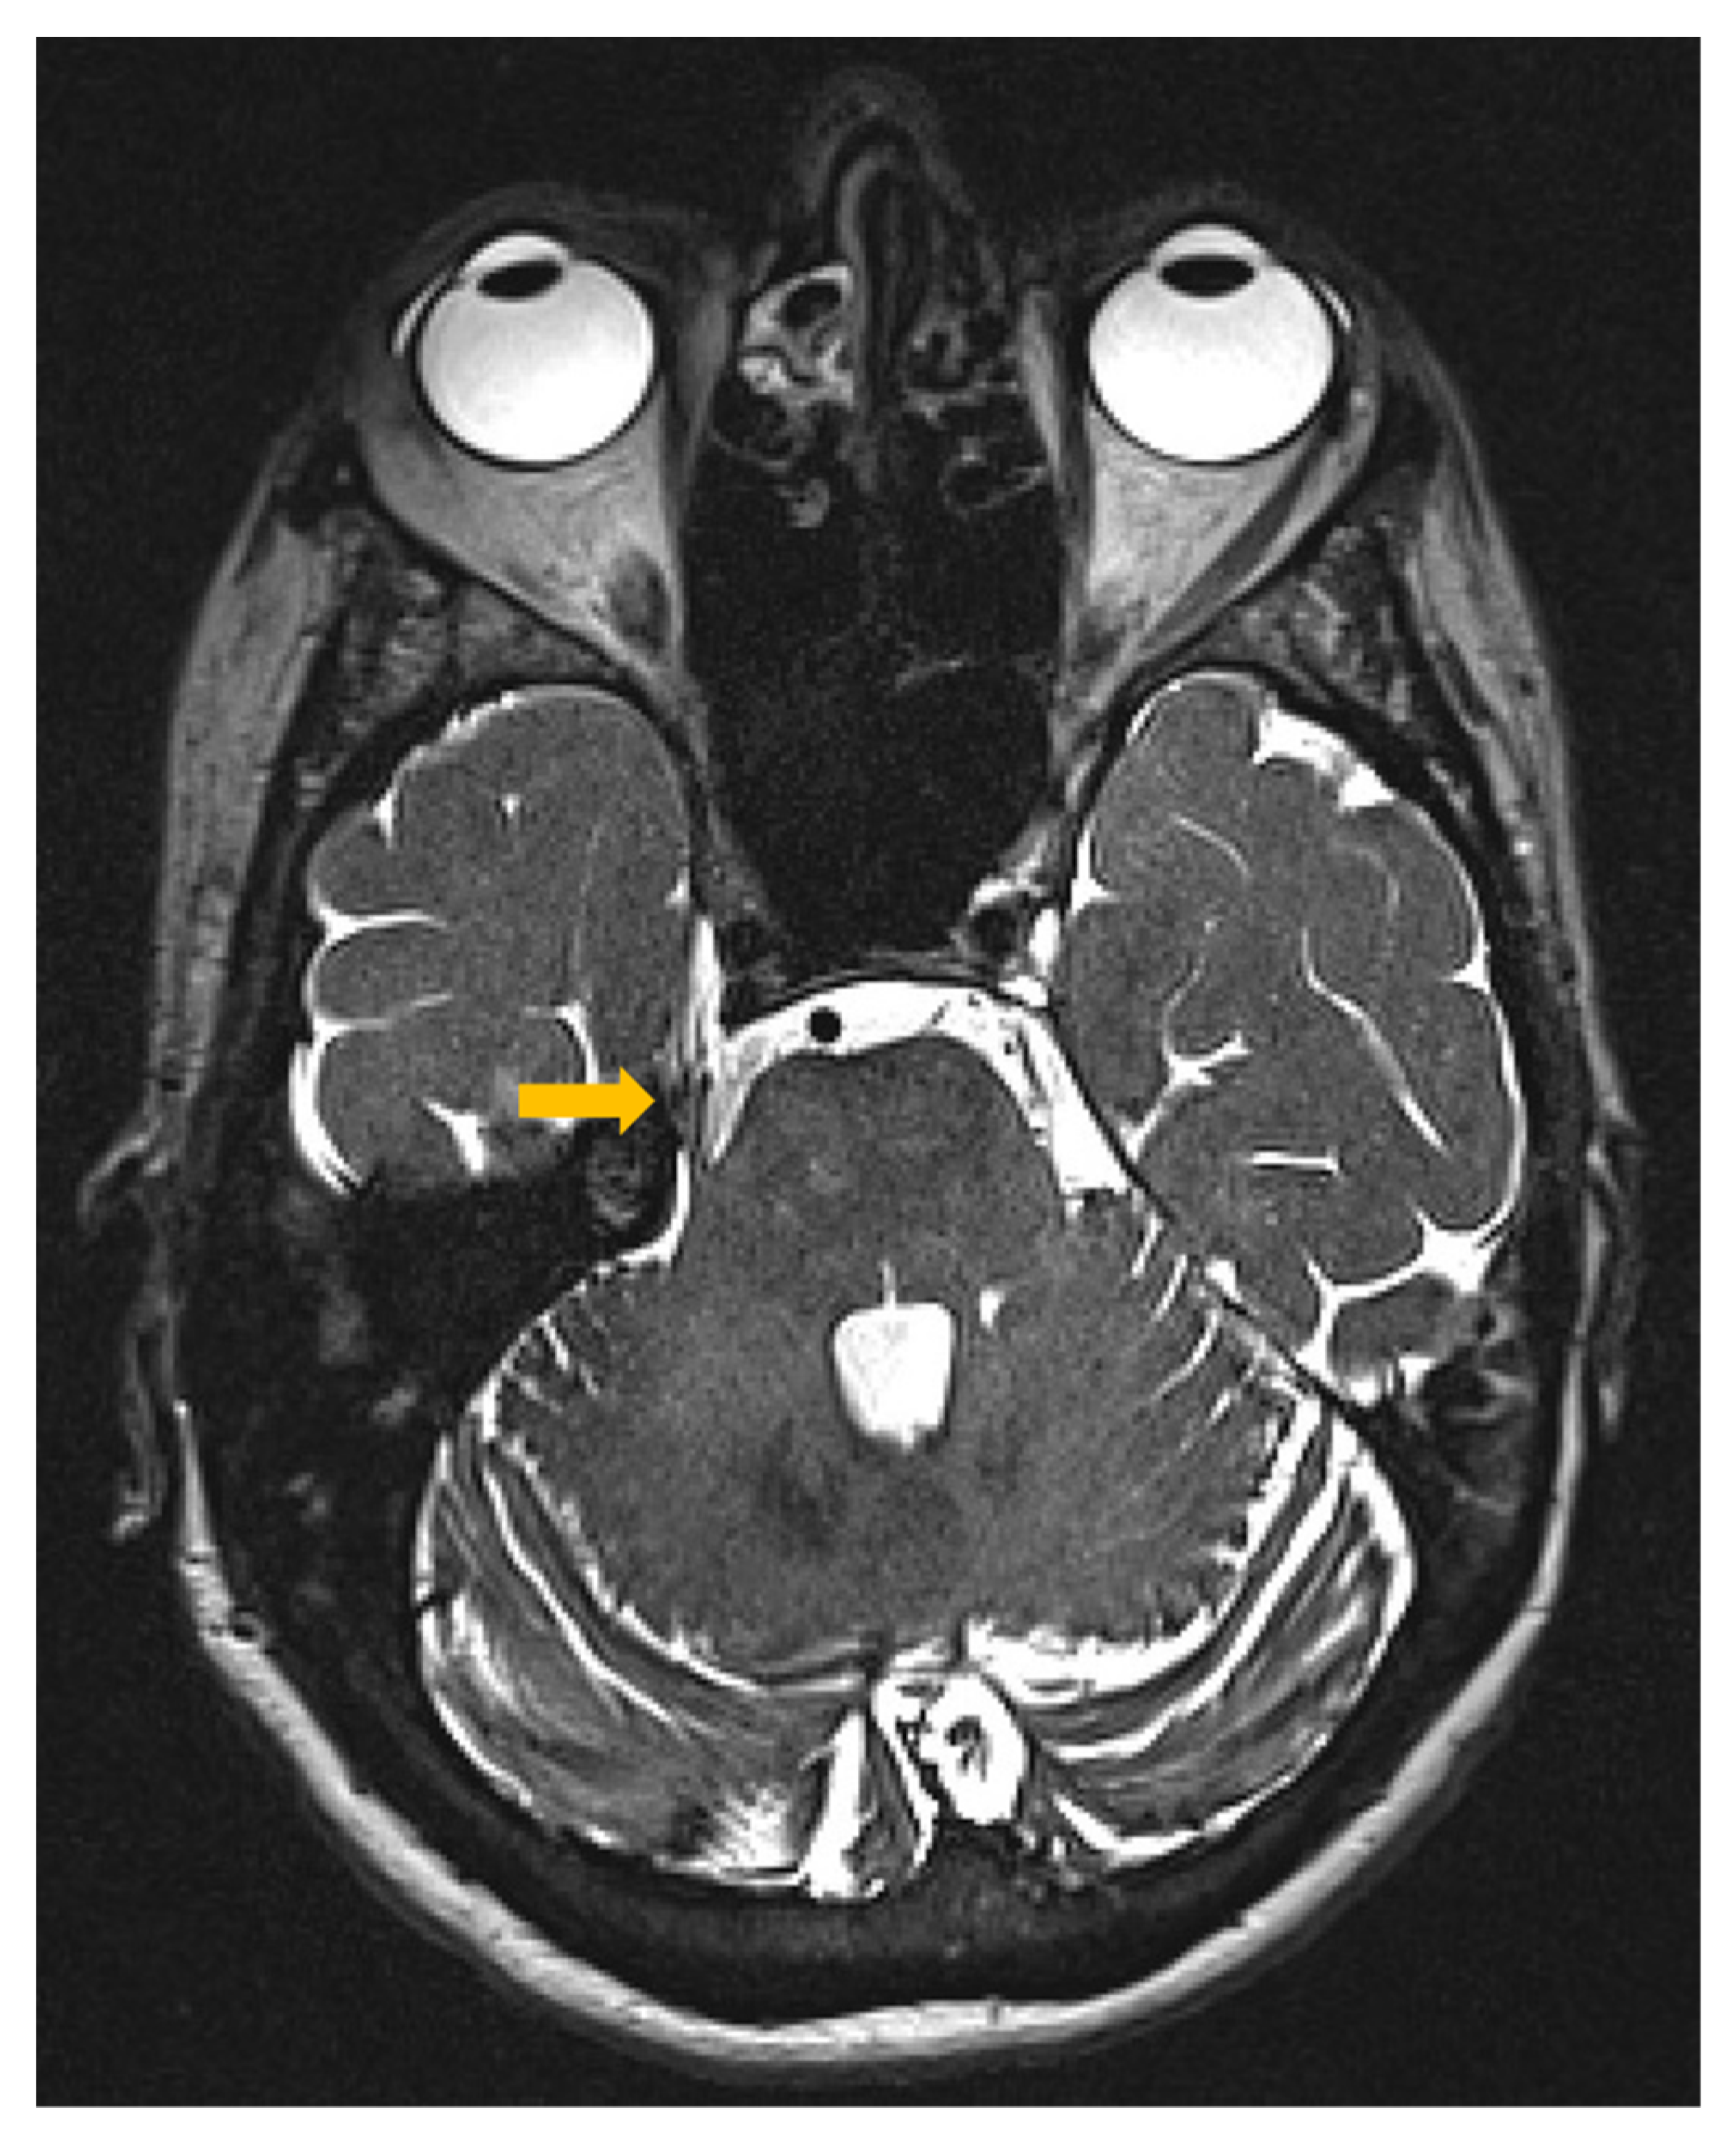

2.1. Patient